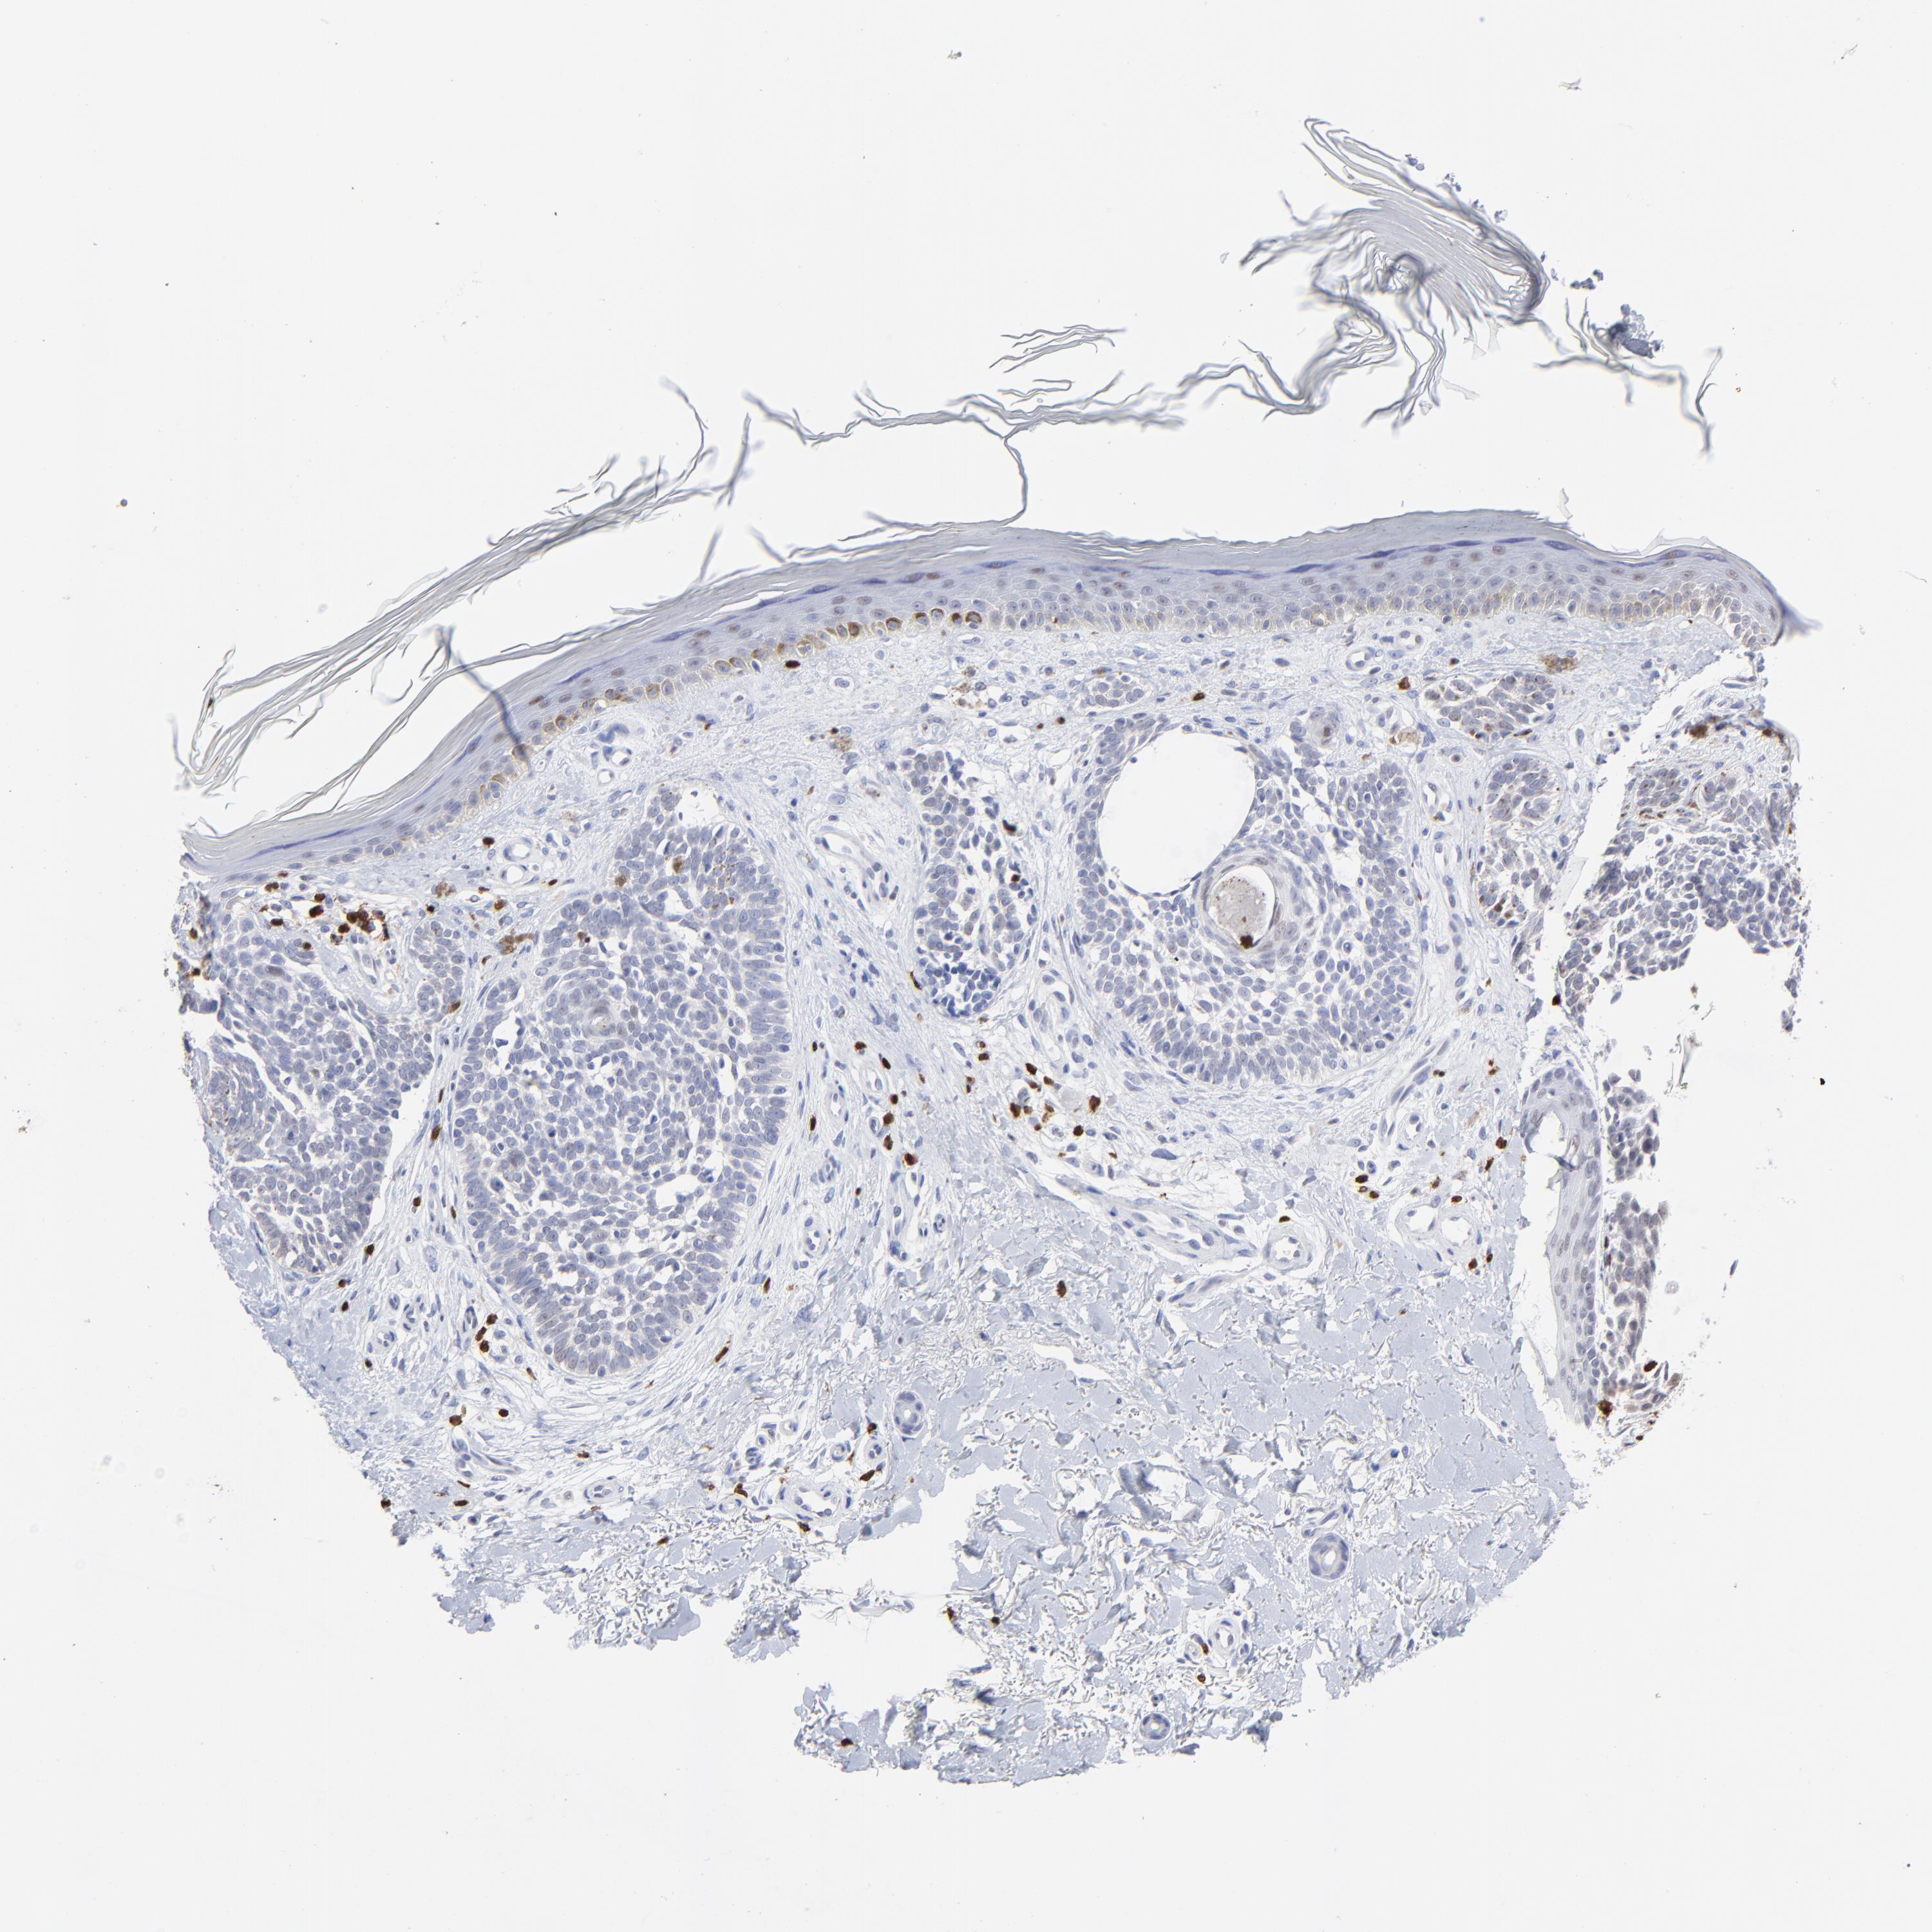

CANCER SKIN CANCER Show tissue menu

SKIN CANCER - Protein expressioni

A mouse-over function shows sample information and annotation data. Click on an image to view it in a full screen mode. Samples can be filtered based on level of antibody staining by selecting one or several of the following categories: high, medium, low and not detected. The assay and annotation is described here.

Antibody stainingi

Antibody staining in the annotated cell types in the current human tissue is reported as not detected, low, medium, or high, based on conventional immunohistochemistry profiling in selected tissues. This score is based on the combination of the staining intensity and fraction of stained cells.

Each image is clickable and will lead to virtual microscopy that enables deeper exploration of all samples and also displays staining intensity scores, fraction scores and subcellular localization as well as patient and tissue information for each sample.

Antibody HPA003134

Squamous cell carcinoma, NOS

Basal cell carcinoma